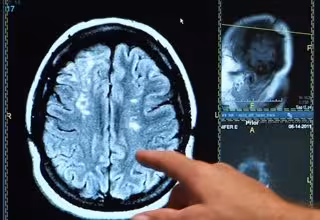

Ictus, derrame cerebral, cerebro

ONALD REAGAN UCLA MEDICAL CENTER